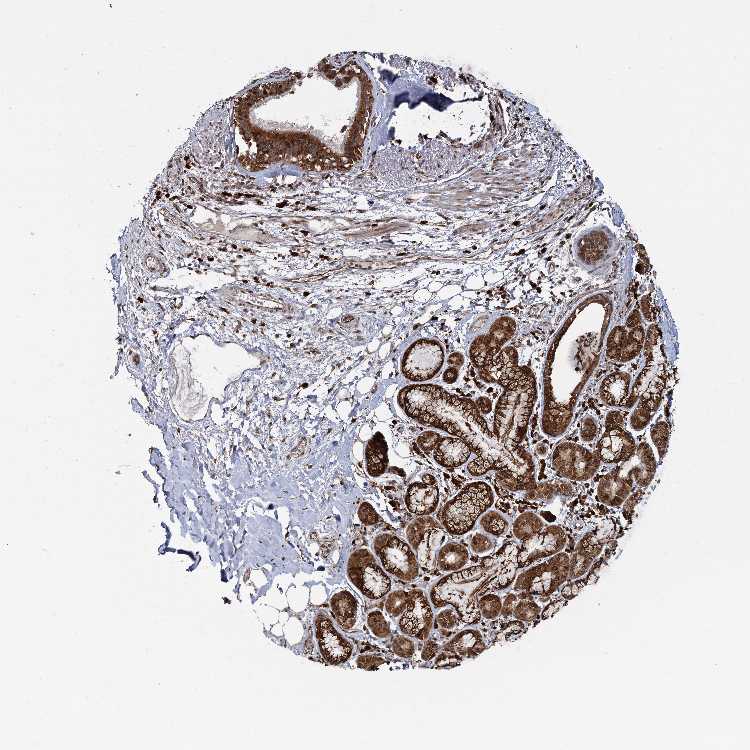

SOFT TISSUE 1 - Antibody stainingi

Antibody staining in the annotated cell types in the current human tissue is reported as not detected, low, medium, or high, based on conventional immunohistochemistry profiling in selected tissues. This score is based on the combination of the staining intensity and fraction of stained cells.

Each image is clickable and will lead to virtual microscopy that enables deeper exploration of all samples and also displays staining intensity scores, fraction scores and subcellular localization as well as patient and tissue information for each sample.

Antibody HPA039004

Fibroblasts High

Peripheral nerve Low

SOFT TISSUE 2 - Antibody stainingi

Peripheral nerve Medium